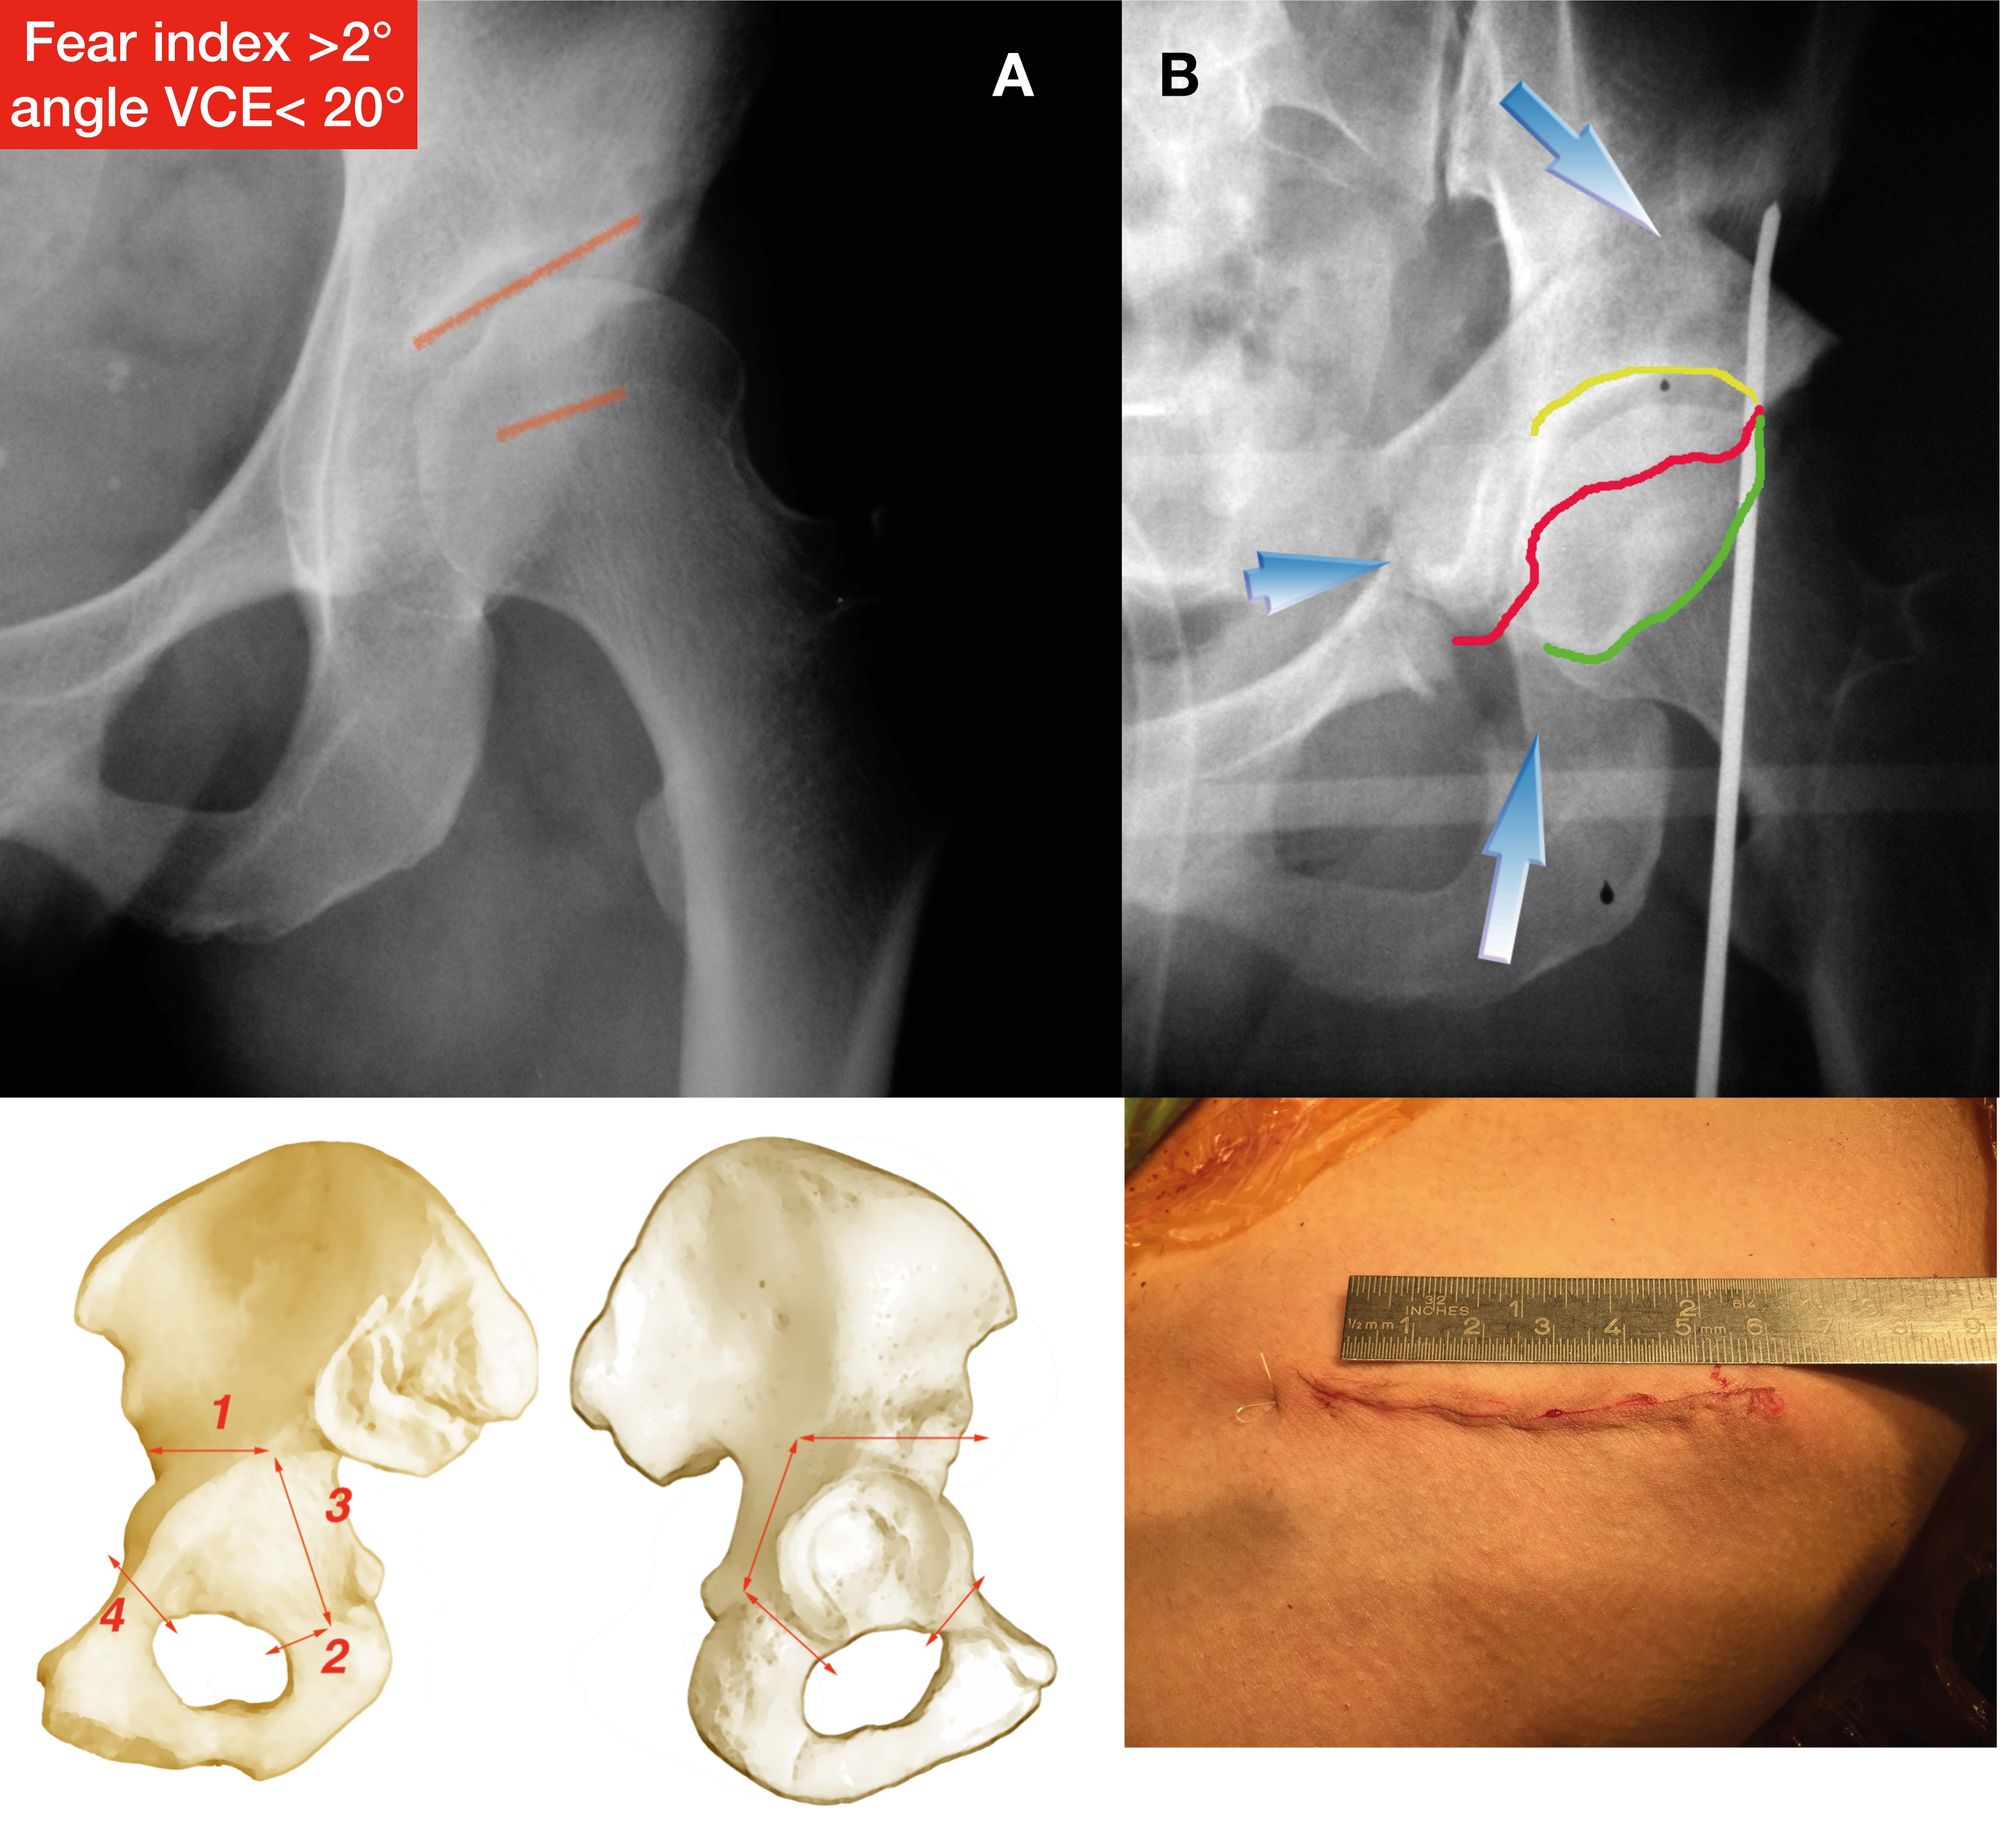

Imaging diagnosis

One can never overestimate the benefits of good standard x-rays and the misery that can be caused by sophisticated but badly performed or misinterpreted tests (CT scans and MRI). The only way to get a perfect assessment is from an expert radiologist working in conjunction with one of the rare orthopaedic surgeons with an interest in this topic (23-25). The first standard x-rays should be standing frontal pelvic views, a Lequesne’s false profile and a Dunn view to assess any accompanying femoroacetabular impingement. The frontal pelvic and false profile views are used to calculate acetabular coverage and identify dysplasia. Coverage less than VCE 25° is suspicious, and an angle of less than 20° as well as a acetabular roof angle > 10° are frankly concerning because it often means that the acetabular bony coverage or position will have to be corrected (Fig. 11). A blunt acetabular rim is also highly suggestive of instability.

Martin Beck (26) has recently described another excellent sign of instability, known as the FEAR index (Femoro Epiphyseal Acetabular Roof) which is the angle between the acetabular sourcil and the femoral head physeal scar (Fig. 12).

The idea came from the fact that during adolescence, the epiphyseal growth plate of the femur orients itself perpendicularly to the forces applied to it, and thus to the acetabulum. If the hip is unstable and subluxes, the growth plate is no longer parallel to the roof of the acetabulum. A recent study has validated this radiological sign in a group of 150 patients undergoing arthroscopy. The FEAR index was significantly more positive in the unstable hips compared with the stable ones (27). Finally, another excellent sign to be aware of, again described by Marc Safran, is the Cliff Sign (28). An unstable hip will nearly always have a very narrow neck and a head that is no longer a perfect circle, losing some sphericity where it ‘exits’ the acetabulum i.e. around its lateral aspect (Fig. 15). The larger the lateral empty space, the greater the sign.